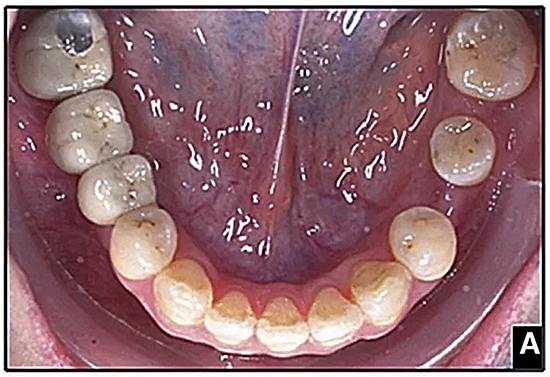

經(jīng)過32個月的活動治療后,上下牙弓排齊良好,下頜第一磨牙區(qū)的雙側(cè)牙間隙可用于種植(圖12,A和13,A)。

治療結(jié)果

該患者獲得了理想的功能和美觀。

成人正畸患者通常有缺牙和牙槽骨萎縮。假設(shè)相鄰的牙齒是牙周健康的,可以通過正畸牙齒移動擴大狹窄的牙脊。該過程是通過牙周膜牽引以產(chǎn)生束骨:骨內(nèi)礦化的膠原束(Sharpey's纖維)。當牙根表面與萎縮牙槽骨的致密骨皮質(zhì)接觸時,牙根側(cè)面吸收是常見的。使用輕力使下頜前磨牙的平移可減少牙周膜壞死和牙根側(cè)面吸收,但這也大大提高了牙齒移動的速度。當牙齒之間的間隙被打開形成種植位置時,新形成的牙槽嵴主要是未成熟的束骨,并且一旦形成就開始在高度和頰側(cè)寬度上萎縮。在種植體植入時建議牙槽嵴骨移植以補償預(yù)期的額外骨質(zhì)流失。強烈建議使用固定保持器進行間隙保持,直到種植體支持式修復(fù)體的完成。盡管在種植體部位出現(xiàn)骨和軟組織問題,但獲得了極好的總體結(jié)果,差異指數(shù)DI(模型頭測評估)從28分降到了13分。